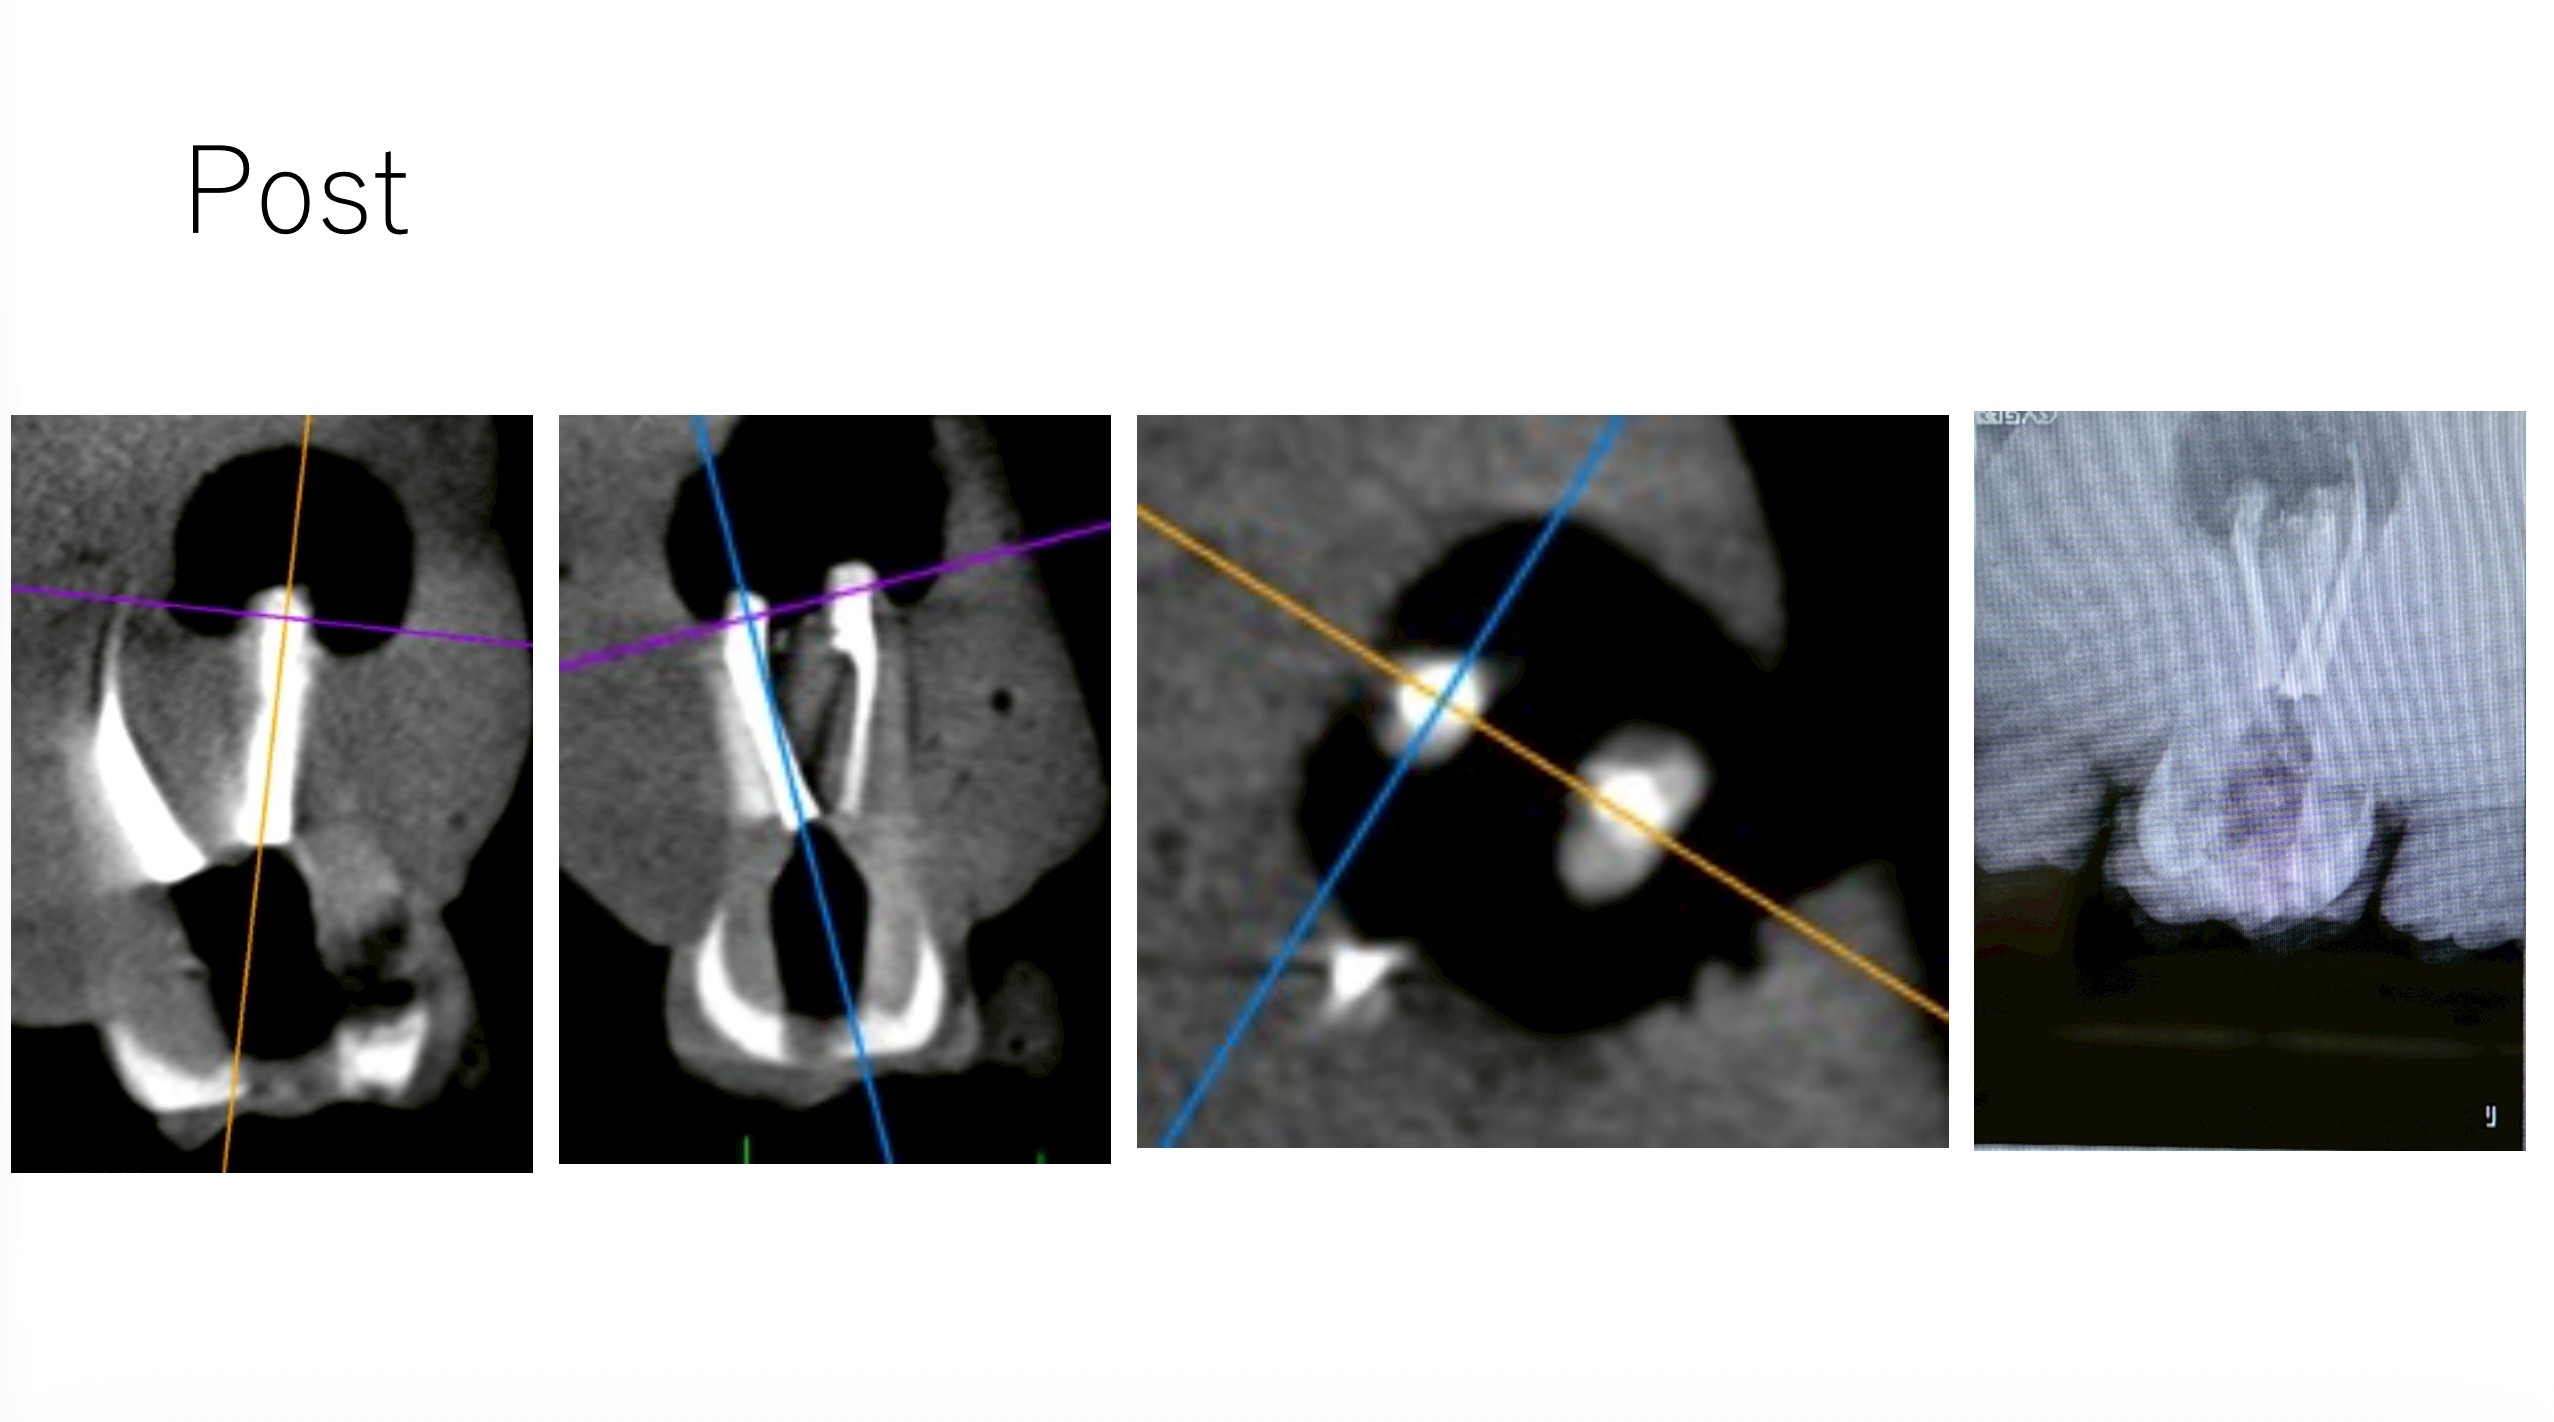

ここで、撮影をしてもらったCBCTを公開しよう。以下である。

これは私なら、もっと切断してやり直すだろう。

絵が、しょっぱいからだ。

Intentional Replantationも問題なくできている。